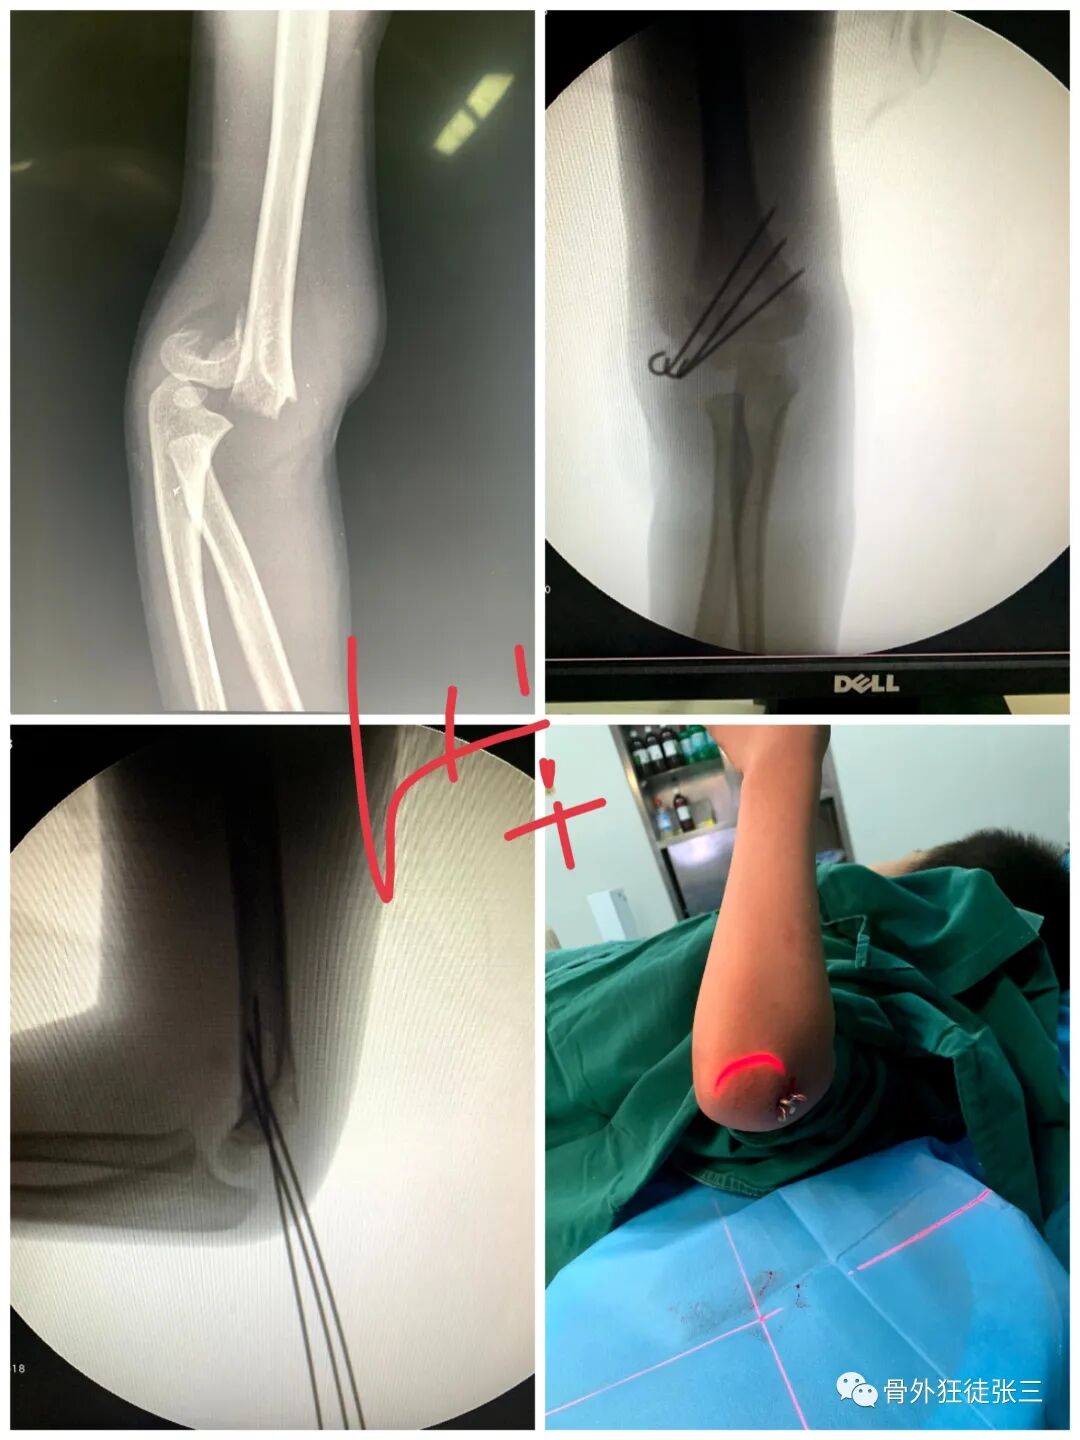

病例14,儿童髁上骨折零切开,桡侧三枚针发散固定

病例15,儿童髁上骨折零切开,

病例16,儿童髁上骨折零切开

病例17,低位髁上骨折零切开

病例24,低位髁上骨折零切开,闭合复位克氏针发散固定

病例25,开放性粉碎性指骨骨折,克氏针固定

病例31,儿童髁上骨折零切开,闭合复位克氏针

病例32,第345掌骨开放性骨折,克氏针髓内+克氏针支架

病例35,3型儿童髁上骨折零切开,闭合复位克氏针

病例38,儿童髁上骨折零切开,克氏针发散固定

病例46,尺骨鹰嘴骨折,克氏针张力带

病例52,高位髁上骨折零切开,闭合穿针

53,儿童髁上骨折零切开,交叉针